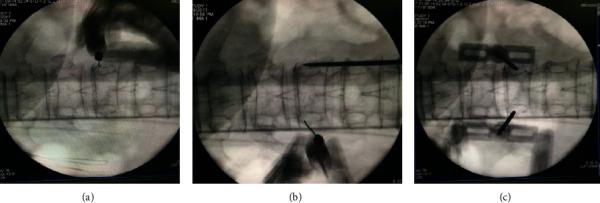

A total of 45 patients (53 vertebral bodies were included) were divided into two groups. Group A included 24 patients (29 vertebral bodies) with an average of 71 years old and Group B included 21 patients (24 vertebral bodies) with an average of 74 years old. Visual analogue scale (VAS) scores were recorded preoperatively; balloon expansion and bone cement injection were conducted intraoperatively. Then, they were recorded immediately after operation, 6 h postoperatively, to assess the pain level of the patient. Moreover, hospitalization time (days), operation duration (minutes), and bone cement injection amount (mL) had also been recorded.

The anesthesia method by injection of 1% lidocaine hydrochloride (5 ml) into vertebral body can effectively relieve patients' pain in intraoperation and postoperation.